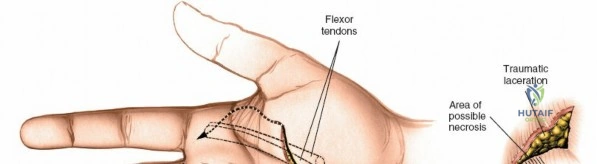

- Exposure of the Fibrous Flexor Sheath for Drainage of Pus: In cases of pyogenic flexor tenosynovitis, surgical incision and drainage are critical to prevent tendon necrosis and osteomyelitis. The volar approach allows thorough irrigation and debridement of the sheath.

Landmarks and Incision

Surface landmarks guide the incision. In the digits, these include the distal phalangeal crease (just proximal to the distal interphalangeal joint), the proximal interphalangeal crease, and the metacarpophalangeal crease. In the palm, the distal palmar crease and thenar/hypothenar creases are important.

The skin incision must provide adequate exposure without creating straight lines across joint creases, which can lead to scar contracture. The Bruner zigzag incision is the standard for digital access due to its excellent exposure and prevention of flexion contractures. It incorporates the natural creases and extends proximally and distally in a zigzag fashion along the length of the digit. The apices of the V's are typically located over the mobile skin of the phalanges, avoiding the fixed skin over the joint creases.

- Finger Incision (Bruner): Begins dorsally/mid-laterally over the distal phalanx, angles volarly, crosses the volar skin crease, then angles back to the mid-lateral line, avoiding straight lines across joints. This allows creation of triangular skin flaps.

- Palmar Incision: Can be made as a curvilinear extension from the digital Bruner incision, often curving towards the thenar or hypothenar eminence, or as a transverse incision in line with the distal palmar crease. Incorporating a laceration directly into the incision is always preferred to minimize additional skin damage.

After marking the incision, the skin and subcutaneous tissues are carefully incised. In the digits, the triangular skin flaps created by the Bruner incision are elevated using fine skin hooks or small self-retaining retractors. Dissection should proceed in the subcutaneous plane, superficial to the digital neurovascular bundles, which run along the radial and ulnar borders of the digit, immediately adjacent to the flexor sheath.

Care must be taken to identify and protect these bundles. Any existing lacerations or hematomas are debrided. The digital nerves and vessels are carefully dissected free from the surrounding connective tissue and retracted, typically dorsally and laterally, using vessel loops or fine retractors to provide clear access to the underlying flexor sheath.

Fibrous Flexor Sheath Exposure

Once the subcutaneous tissue and neurovascular bundles are retracted, the fibrous flexor sheath is visible. This appears as a glistening white, tough structure enveloping the flexor tendons.

- Infection Drainage: For pyogenic flexor tenosynovitis, the sheath is incised longitudinally along its entire length, and thorough irrigation with saline solution is performed. Tissue samples are sent for culture.